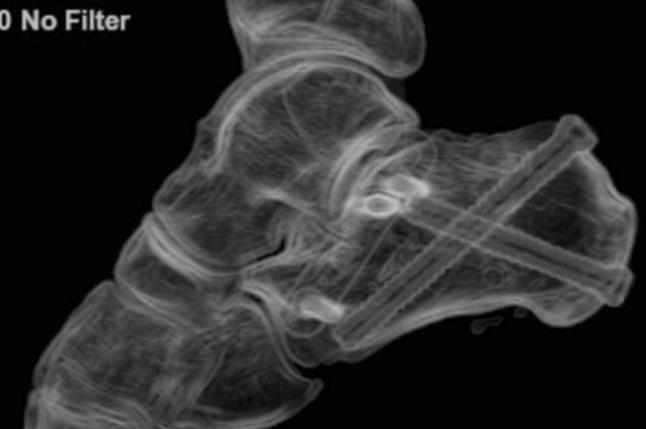

Calcaneal fractures: Where are we now?

This review article on the current management for calcaneal fractures discusses the advantages and disadvantages of different treatment options including the problems encountered. Controversies are described and the evidence reviewed. The management of some types of displaced intra-articular calcaneal fractures remains contentious; is there a preferred stabilisation method for each type of calcaneal fracture? How constant is the "constant fragment" in an intra-articular calcaneal fracture and what is the evidence for primary arthrodesis and what is its place in these fractures?